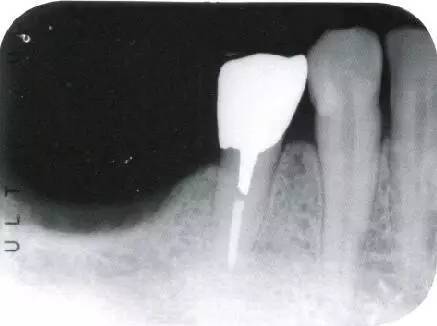

牙齿侧穿图片,根管侧穿图片

46去除颌面暂封物后,远中壁尚存,未侧穿

根管侧穿图片

根管治疗侧穿图片